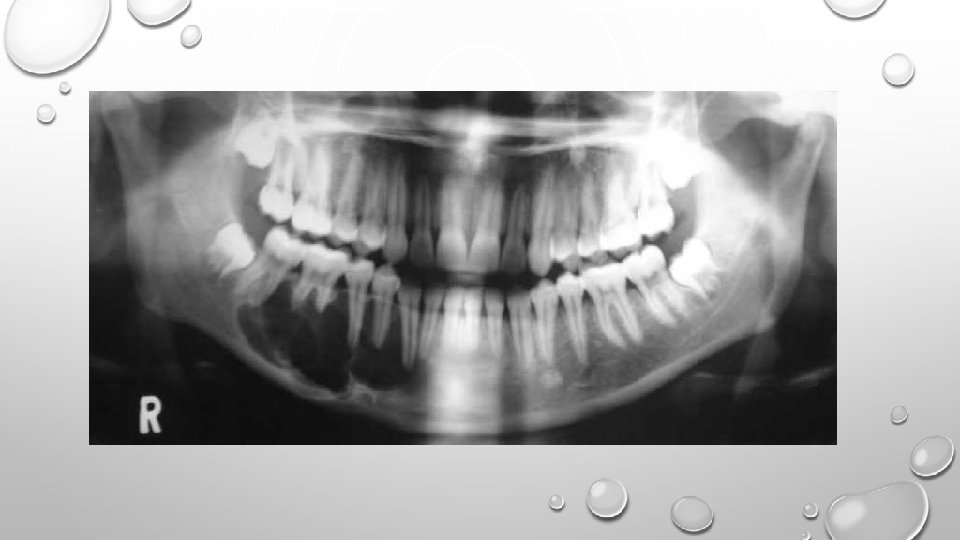

AMELOBLASTOMA: • It is an odontogenic tumor representing approx. 11% to 13% of the odontogenic tumors. • It is bony-hard and non-tender on palpation. • Unicystic or mural ameloblastoma forms in the wall of a dentigerous cyst. • Radiographically, a unilocular or multilocular radiolucency is seen. Soap-bubble or honey-comb appearance is characteristic.

CEMENTOBLASTOMA: • It is a cementum-producing lesion which is fused to the root of a vital tooth. • Often occurs in young adults and in association with a mandibular molar or premolar. • Pain is a frequent complaint. • Radiographically, it demonstrates a pathogonomic appearance – a well-defined radiopaque mass surrounded by a radiolucent halo that incorporates root of the tooth.